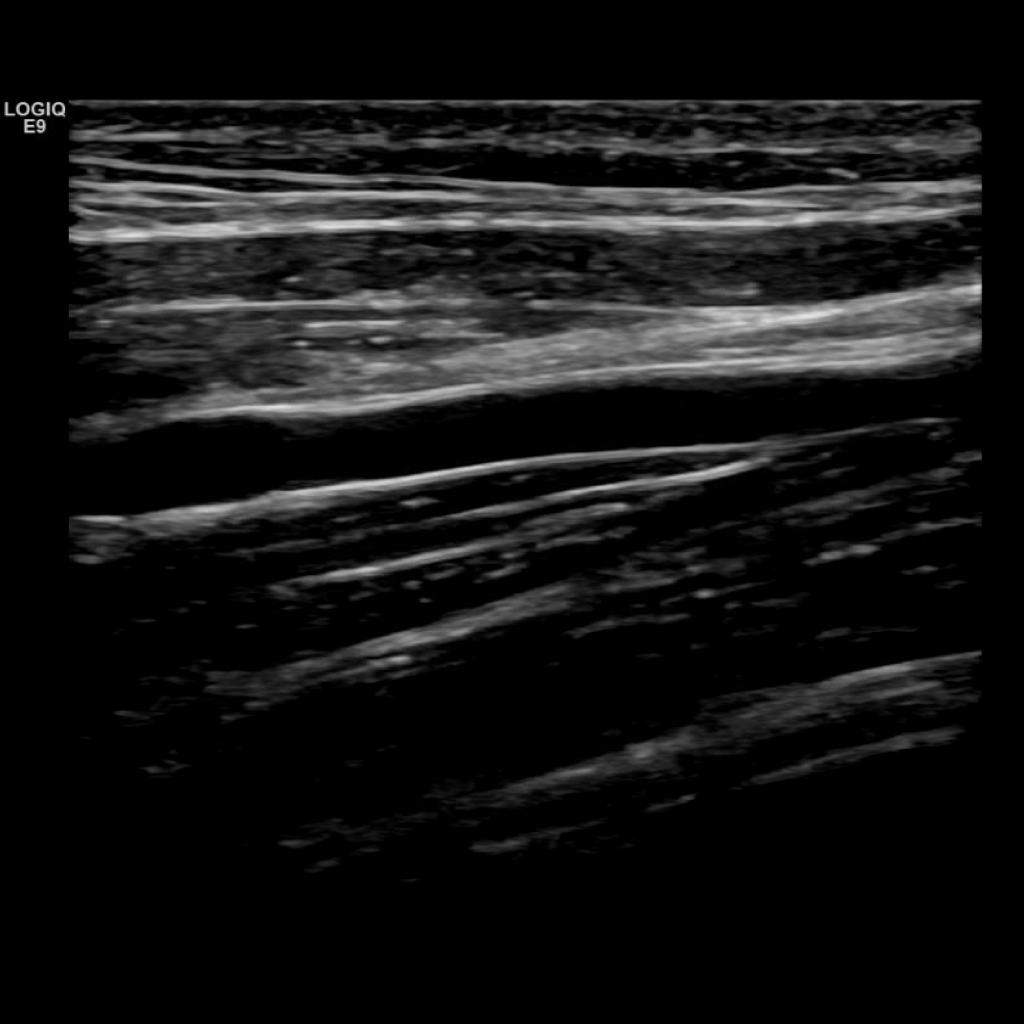

A typical scanning protocol includes transverse and sagittal images with and without color doppler and spectral wave analysis of the IJV, subclavian, axillary, brachial, basilic, cephalic, radial and ulnar veins. In my institution we include innominate and superior vena cava (SVC) in the vessels we interrogate.

Scan the basilic vein in grey scale, compression, color doppler and spectral doppler

Scan the brachial veins in grey scale, compression, color doppler and spectral doppler